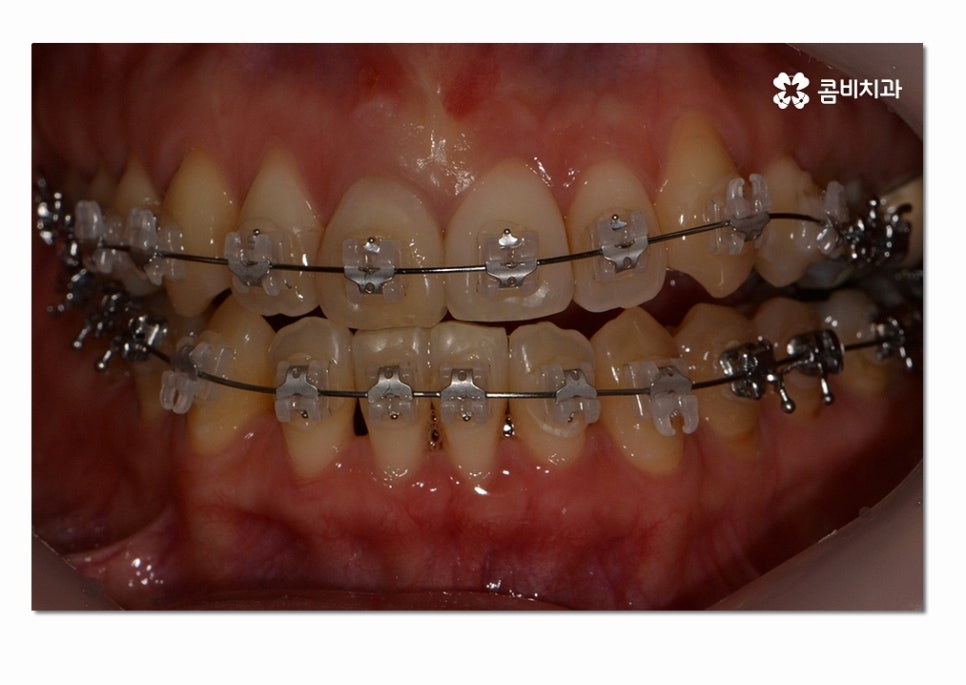

위 사례의 경우에는 3급 부정교합의 케이스로

치열이 맞지 않아 치아의 본래 기능들이 제대로 이루어지지 않고 있는 상태이며

서로 닿지 않아서 식사를 할 때마다 제대로 씹지 못하여

불편함을 느끼는 것은 물론이며 구강관리도 잘되지 않아서

충치가 많이 발생하고 있는 사례였다고 볼 수 있어요.

위 환자분의 경우에는 클리피씨 교정 장치를 통해서 치료가 진행되었으며

발치와 수술 없이 3급 부정교합을 개선한 사례라고 할 수 있어요.

치료에 사용된 클리피씨 장치의 경우 치료 기간을 단축시키고

초기 통증을 감소시킨다는 점과 심미성도 우수한 편이라는 장점이 있는데요.